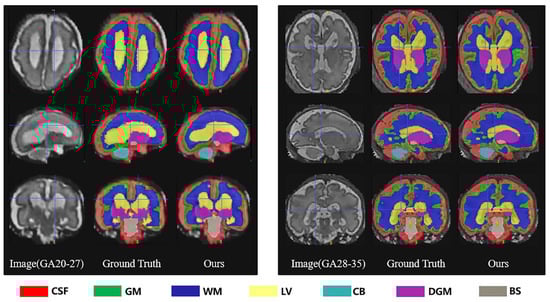

Each case consisted of a 3D superresolution reconstruction of the fetal brain (256 × 256 × 256 voxels). Training cases had an annotated label map corresponding to 7 different brain tissue types: external cerebrospinal fluid (eCSF), gray matter (GM), white matter (WM), lateral ventricles (LV), cerebellum (CB), deep gray matter (DGM), and brainstem (BS). As shown in Figure 1 below.

Figure 1.

An example of manual segmentation (red: external cerebrospinal fluid; green: GM; dark blue: WM; yellow: ventricles; cyan: cerebellum; maroon: deep GM: gray: brainstem).